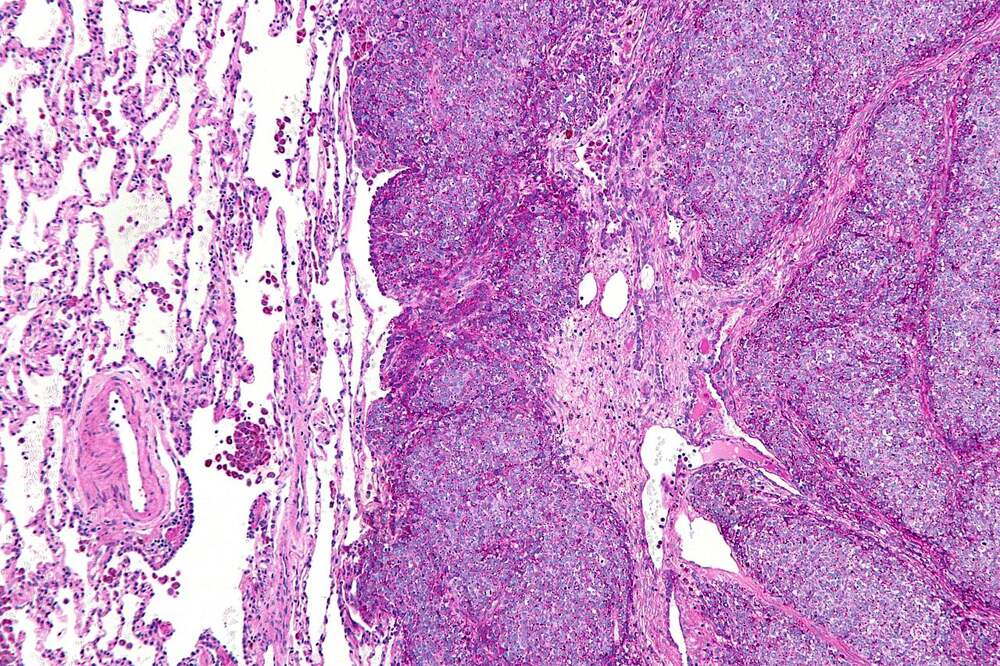

Сеченовские учёные предложили новый способ лечения устойчивой саркомы Юинга

Учёные Сеченовского университета разработали систему доставки препаратов, которая усиливает противоопухолевый эффект и воздействует на клетки саркомы Юинга, нечувствительные к стандартной химиотерапии; результаты опубликованы в журнале Nanomedicine: Nanotechnology, Biology and Medicine (см.... Далее